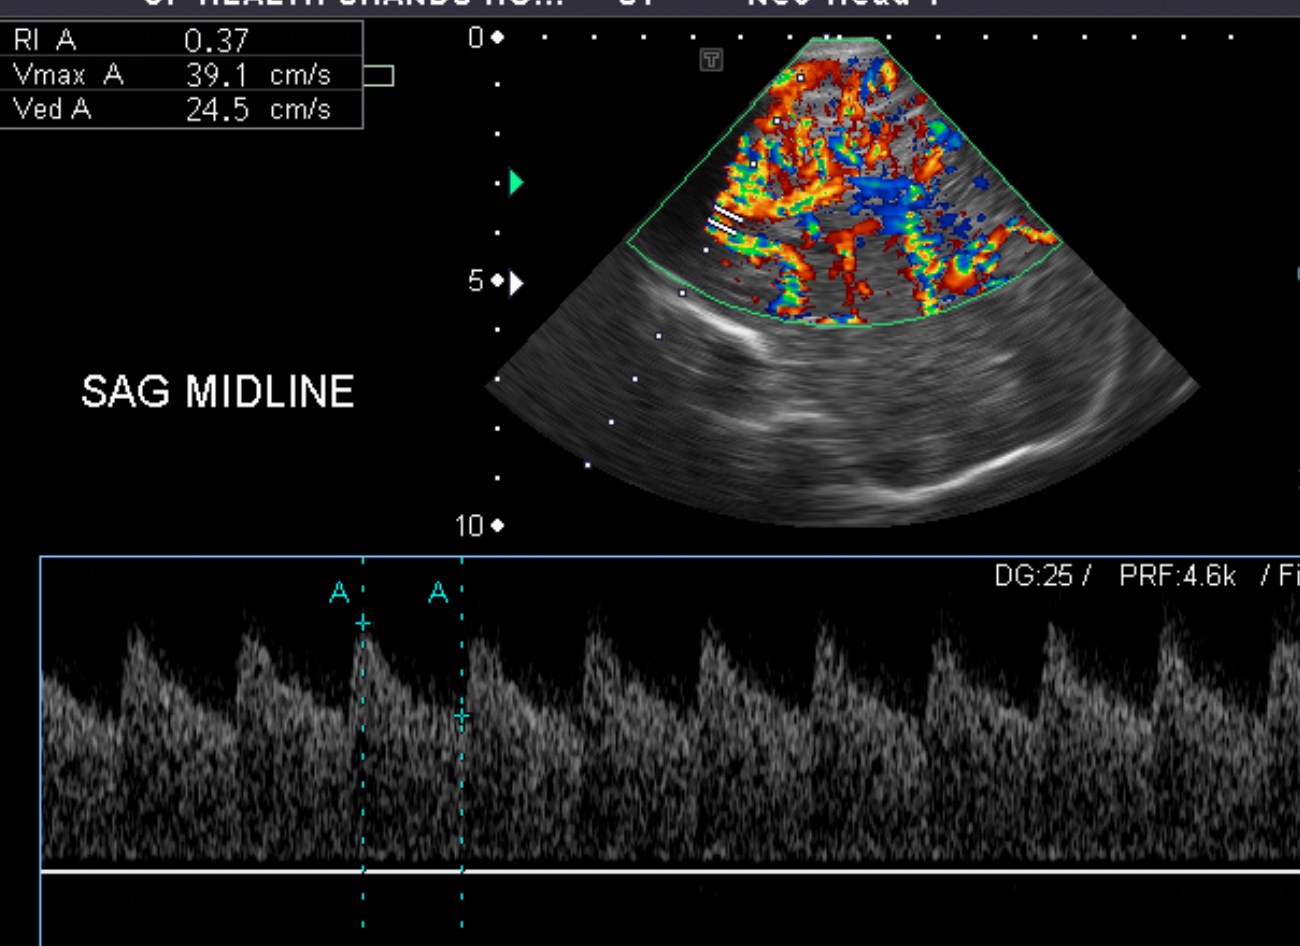

Section 1 Submit Findings Case151 Findings Brain The brain is immature. Yes No There is under-sulcation and open sylvian fissures. Yes No There is/are multiple hypoechoic areas in the periventricular white matter. Yes No There is/are multiple hyperechoic areas in the periventricular white matter. Yes No There is diffuse cerebral edema with diffusely increased echogenicity of the brain parenchyma and loss of grey white matter differentiation. Yes No The thalami/basal ganglia are hypoechoic. Yes No There is periventricular calcification. Yes No There is intra-parenchymal calcification. Yes No CSF spaces/ventricular system There is a prominence of the extra axial fluid spaces. Yes No There are debris/septations in the extra axial fluid spaces. Yes No There are debris/septations in the ventricles. Yes No There is a subdural collection on the right/left side. Yes No There is prominence of the ventricular system. Yes No There is an asymmetry of the ventricular system. Yes No There is a cavum septum pellucidum. Yes No There is a midline shift towards right/left. Yes No The choroid plexus is bulky/lobulated. Yes No There is a choroid plexus cyst measuring… Yes No There are debris/clots in the occipital horn. Yes No There is a posterior fossa cyst measuring… Yes No The tentorium is elevated/depressed. Yes No The lateral ventricle/s are dilated. Yes No The third ventricle is dilated. Yes No The 4th ventricle is dilated. Yes No There are pseudo cysts. Yes No Germinal matrix hemorrhage (Only in the premature infants): Please do not answer if the patient is a full term. There is a germinal matrix hemorrhage, consistent with a grade I hemorrhage. Yes No There is an intraventricular extension consistent with a grade II hemorrhage. Yes No There is an intraventricular extension with the dilatation of ventricles, consistent with a grade III hemorrhage. Yes No There is an intra-parenchymal extension, consistent with grade IV hemorrhage. Yes No On color Doppler examination, the Resistive index in the anterior cerebral artery is… There is a loss of the diastolic flow on the Doppler exam. Yes No There is altered vascularity on Doppler imaging. Yes No There is an AVM in the region of… Yes No